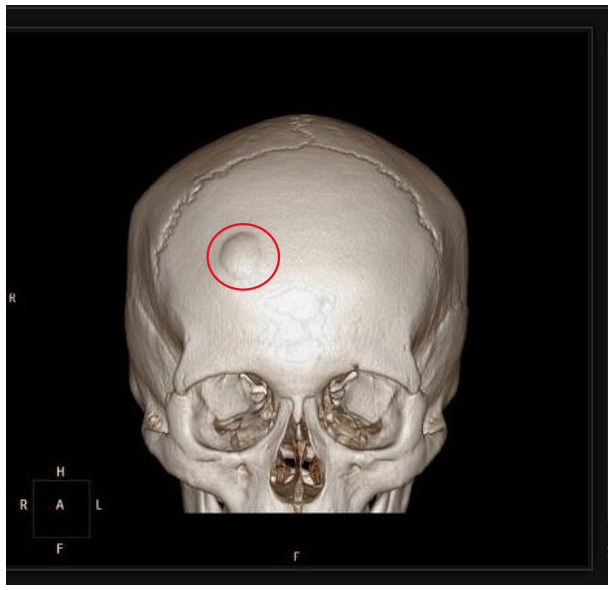

osteoma

bosselated, round sessile tumors that project from the subperiosteal or endosteal surface of cortex

composed of woven & lamellar bone

slow growing

solitary & detected in middle age

Gardner syndrome

a condition characterized by multiple osteomas